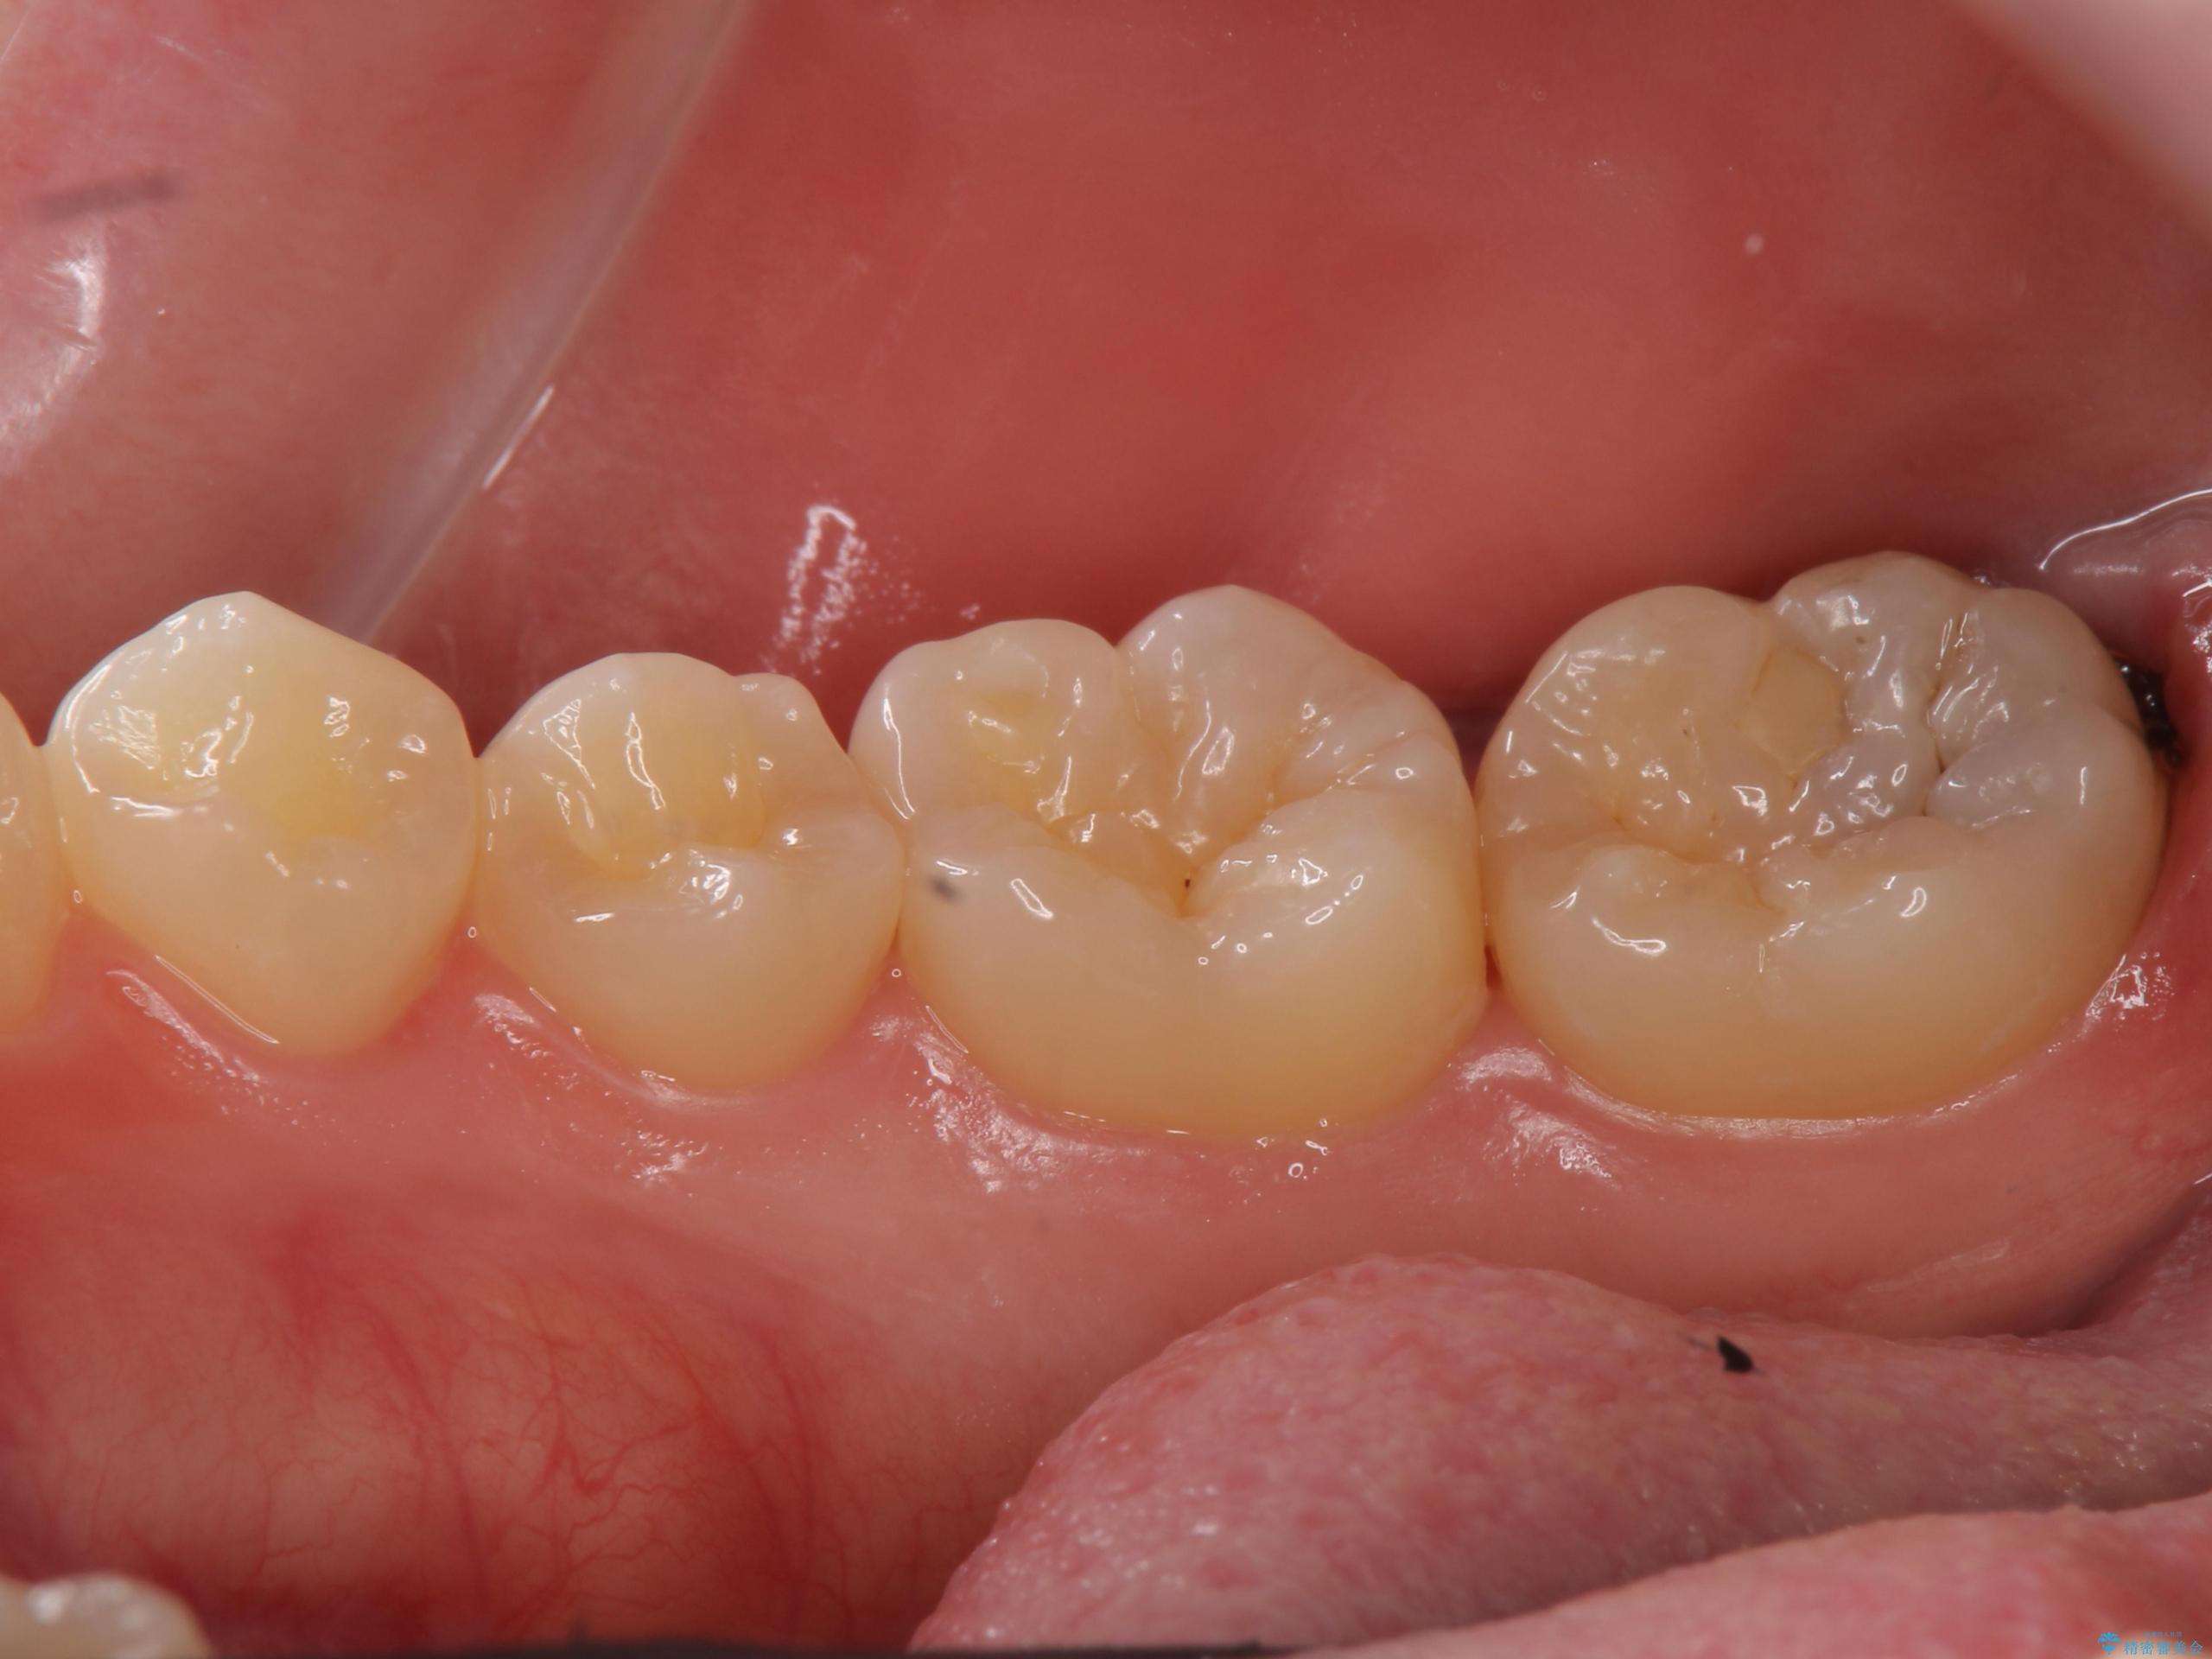

- 検査の結果虫歯が見つかった患者様です。

親知らずを抜歯してから虫歯を除去した後、ゴールドの詰め物で修復します。

比較的大きな虫歯でしたがゴールドでの修復にすることで歯の削る量を抑え、精度の高い治療を行うことができました。

親知らずの問題も同時に解決することで今後の虫歯リスクを抑えています。